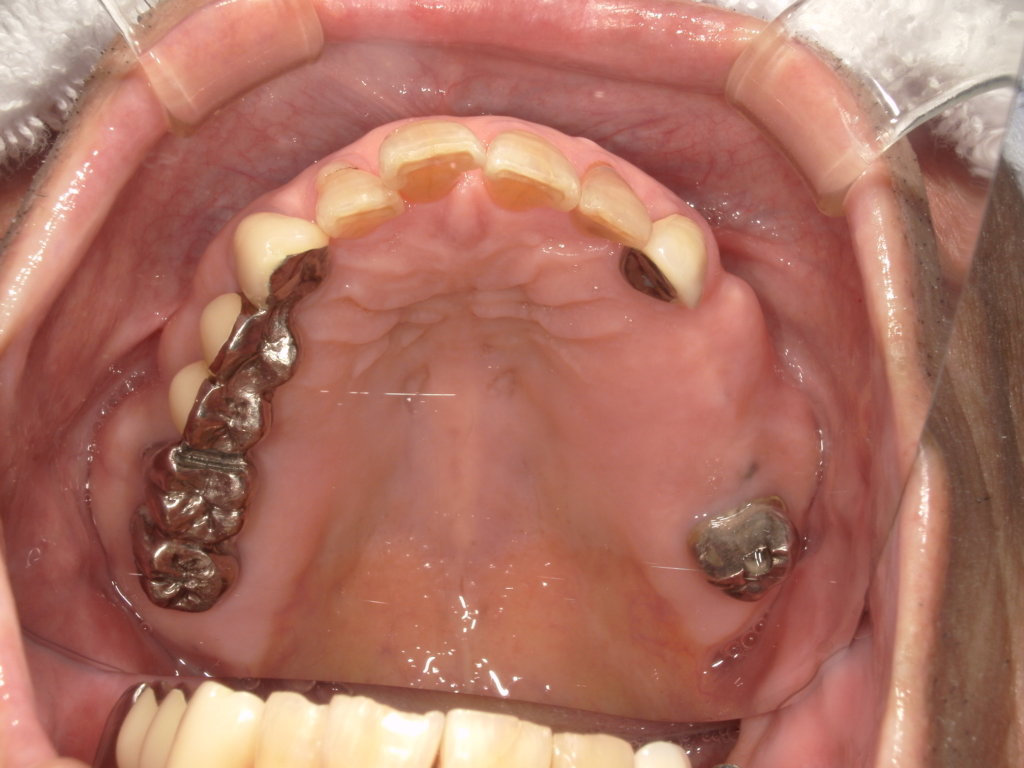

Y様インプラント実例 #44

左の上下の奥歯をインプラントで治療しています。

左下の奥歯は歯を抜くのと同時にインプラントの埋め込みを行っています。

被せものは上下、セラミックスで作っています。

治療前

治療後